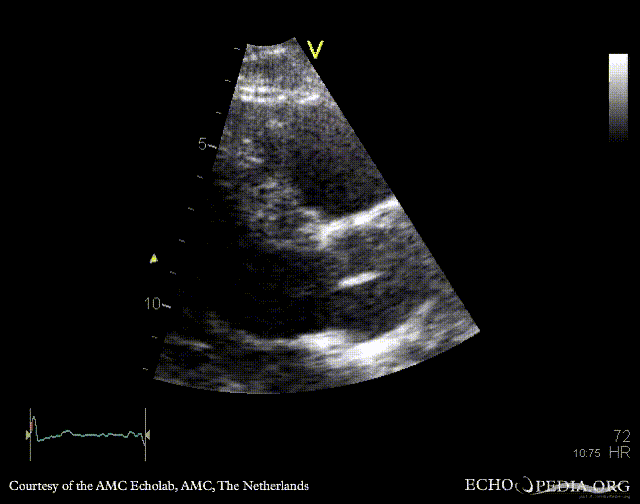

Endocarditis of aortic valve

PLAX: vegetation on aortic valve PSAX: vegetation on aortic valve